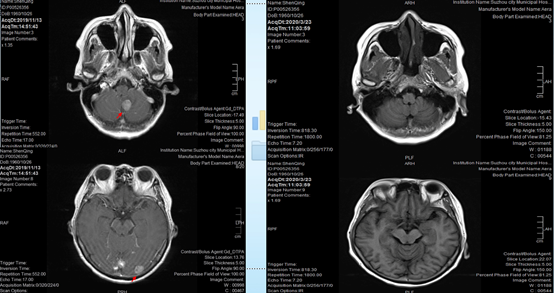

患者自行查阅相关资料后,更换为阿法替尼治疗。同时行胸腔闭式引流,胸腔内注射顺铂,予白蛋白紫杉醇化疗等治疗方案。

2020-10-27,CT复查提示患者胸水较前稍有减少,但仍持续存在。

此次治疗后,患者自行咨询美国MD安德森医生,要求更换治疗方案为,全脑放疗,行胸膜固定术,继续奥希替尼80mg qd。

朱锡旭教授:由于患者的影像学资料不是很全面,所以无法判断脑部病灶是否有进展。但是从随访过程中病人的临床特征来看,没有明显的神经系统侵犯。因此,放疗可以暂时缓一缓,没有必要急着去做。

宋勇教授:放疗是没有必要做的,因为患者的病情稳定,也没有明显的临床症状。即使患者存在脑部病灶,但是患者没有明显的临床症状,也是不应该做放疗的,更不用说患者脑部病灶已经完全吸收了。

那么为什么美国MD安德森癌症中心的医生会建议做全脑放疗呢?我认为,原因可能在于,患者家属在和美国医生沟通时,语言的差异问题以及中美医生在TKI治疗脑转移理念上的差异。

在美国医生看来,对于脑转移患者,还是放疗最靠谱;但是大部分中国医生认为,TKI对于脑转移更靠谱,尤其是将TKI放在放疗之前,待TKI治疗失败后,再选择放疗。